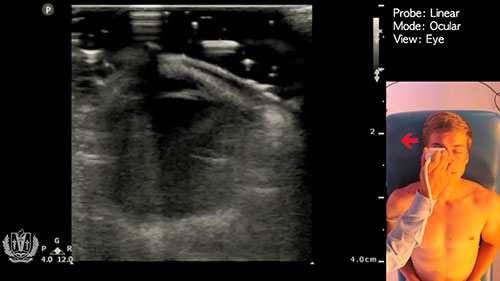

类别:眼视光技术

简介:视力障碍教师解释了为什么带有触觉插图的书籍对视力障碍儿童如此重要。